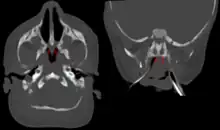

| Bilateral membranous choanal atresia in CT scan | |

Choanal atresia is a congenital disorder where the back of the nasal passage (choana) is blocked, usually by abnormal bony or soft tissue (membranous) due to failed hole development of the nasal fossae during prenatal development. It causes persistent rhinorrhea, and with bilateral choanal atresia and obstructed airway that can cause cyanosis and hypoxia.

Choanal atresia causes closure of the posterior choanae in the nasal cavity.[1] Around 30% of these affect just the bone, while around 70% affect both bone and membranes.[1] Bones affected can include the body of the sphenoid bone, the vomer, the medial pterygoid process of the sphenoid bone, and the horizontal plate of the palatine bone.[1]

Radiology

Diagnosis is confirmed using CT scan.[1][2] This is also useful for differential diagnosis.[1]